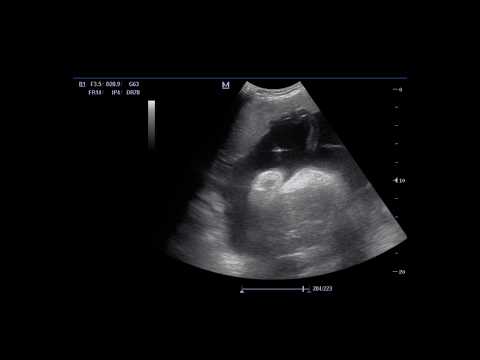

ჭიპლარის ვენაში სისხლის გადასხმა / INTRAUTERINE TRANSABDOMINAL BLOOD TRASNSFUSION

ჭიპლარის ვენაში სისხლის გადასხმა / INTRAUTERINE TRANSABDOMINAL BLOOD TRASNSFUSION 03:48

ჭიპლარის ვენაში სისხლის გადასხმა / INTRAUTERINE TR...